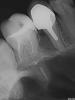

luchik Опубликовано 24 апреля, 2013 Поделиться Опубликовано 24 апреля, 2013 Здравствуйте!На 5-ке ( могу ошибаться с нумерацией) стоит коронка. Последнее время стало иногда несильно ныть между 5 и 6 зубами. Сделали снимок. Сказали воспаление, но из-за чего сказать толком не могут. Предполают, что трещина корня, но на снимке ее не видят. Предлагают удалить и протезировать. Неужели больше ничего нельзя сделать? Зуб жалко! А если воспаление не из-за трещины, то возможен какой-то другой выход или все равно удалять? Ссылка на комментарий

Magdalena Опубликовано 24 апреля, 2013 Поделиться Опубликовано 24 апреля, 2013 Действительно, локализация воспалительного очага похожа на трещину. Вам нужен опытный врач, который может извлечь штифтовкладку и под микроскопом оценить состояние тканей на предмет трещины. Так же можно попробовать посмотреть трещину на компьютерной томограмме. Если тещина - 100% удаление, чем раньше - тем больше сохраниться кости для последующей имплантации. Ссылка на комментарий

Magdalena Опубликовано 12 мая, 2013 Поделиться Опубликовано 12 мая, 2013 Возможно, но воспаление такое большое вряд ли денется куда-то. Сделайте компьютерную томомграмму, может там видно будет трещину. Ссылка на комментарий